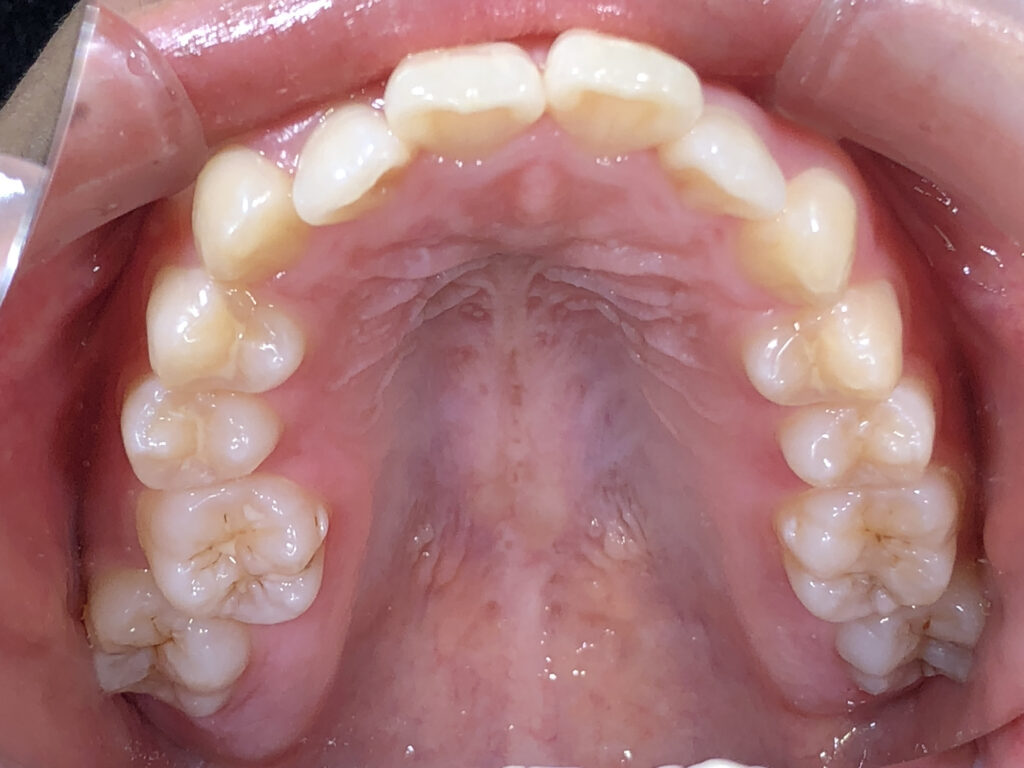

上顎

治療後